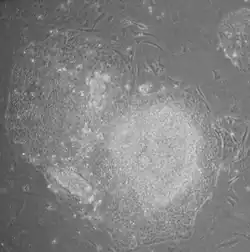

- Morphology: iPSCs were morphologically similar to ESCs. Each cell had round shape, large nucleolus and scant cytoplasm. Colonies of iPSCs were also similar to that of ESCs. Human iPSCs formed sharp-edged, flat, tightly packed colonies similar to hESCs and mouse iPSCs formed the colonies similar to mESCs, less flat and more aggregated colonies than that of hESCs.

iPSC derivation is typically a slow and inefficient process, taking one–two weeks for mouse cells and three–four weeks for human cells, with efficiencies around 0.01–0.1%. However, considerable advances have been made in improving the efficiency and the time it takes to obtain iPSCs. Upon introduction of reprogramming factors, cells begin to form colonies that resemble pluripotent stem cells, which can be isolated based on their morphology, conditions that select for their growth, or through expression of surface markers or reporter genes.